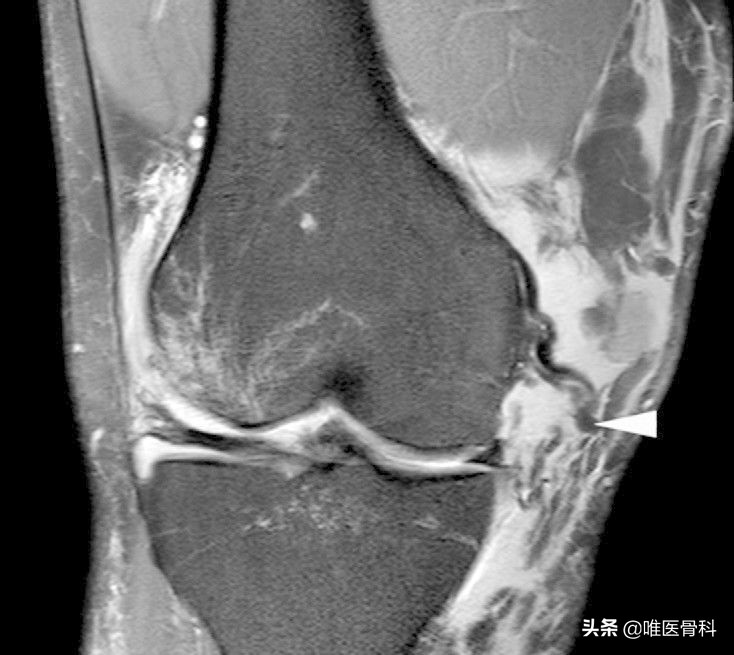

3)膝关节核磁共振:可以比较直接的看到膝关节内、外侧副韧带的损伤程度,同时可以显示是否合并有半月板或交叉韧带的损伤。

膝关节内侧副韧带损伤的诊疗进展,膝关节内侧副韧带损伤的正确叙述